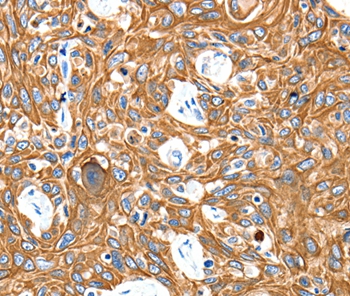

Immunohistochemical analysis of paraffin-embedded Human esophagus cancer tissue using #35615 at dilution 1/20.